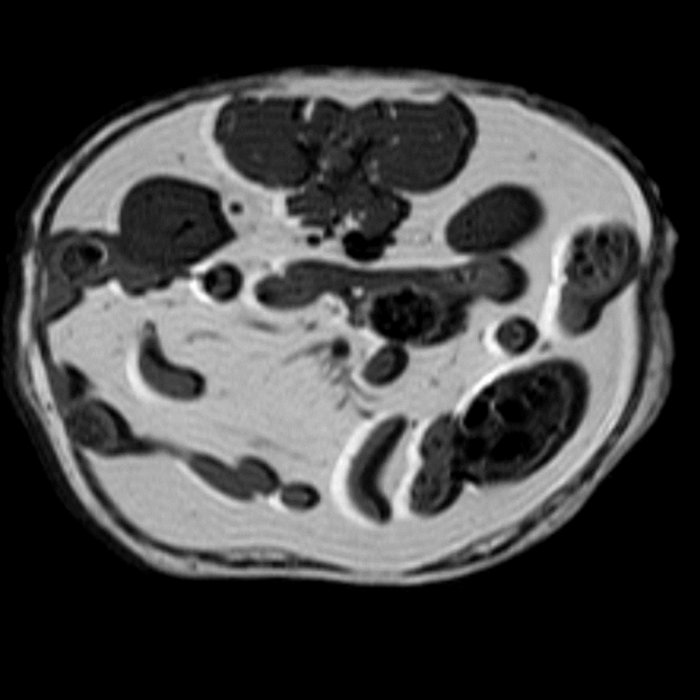

In Vivo MRI Gallery

MRI: Mouse pregnancy